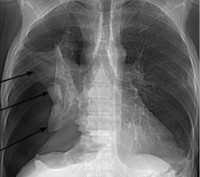

Рассмотрим некоторые специфические симптомы, которые могут возникать при различных формах пневмофиброза. У пациентов с идиопатическим пневмофиброзом могут наблюдаться плотные opacities на рентгенограммах грудной клетки и профузная опухолевая фиброзная оболочка легких. У селян с пневмокониозом возникают грубые и пигментированные бляшки облитающие корни легких. А при радиографическом осмотре у пациентов с пневмофиброзом, обусловленном профессиональными раздражителями, будет видно утолщение иреальной хлопка, длинных легочных магистралей, наличие способных макронодулярных образований с протравленными центрами.

Диагностика пневмосклероза включает анализ клинических симптомов, физикальное обследование, рентгенографию и компьютерную томографию (КТ) легких. Иногда может потребоваться биопсия легкого для подтверждения диагноза.